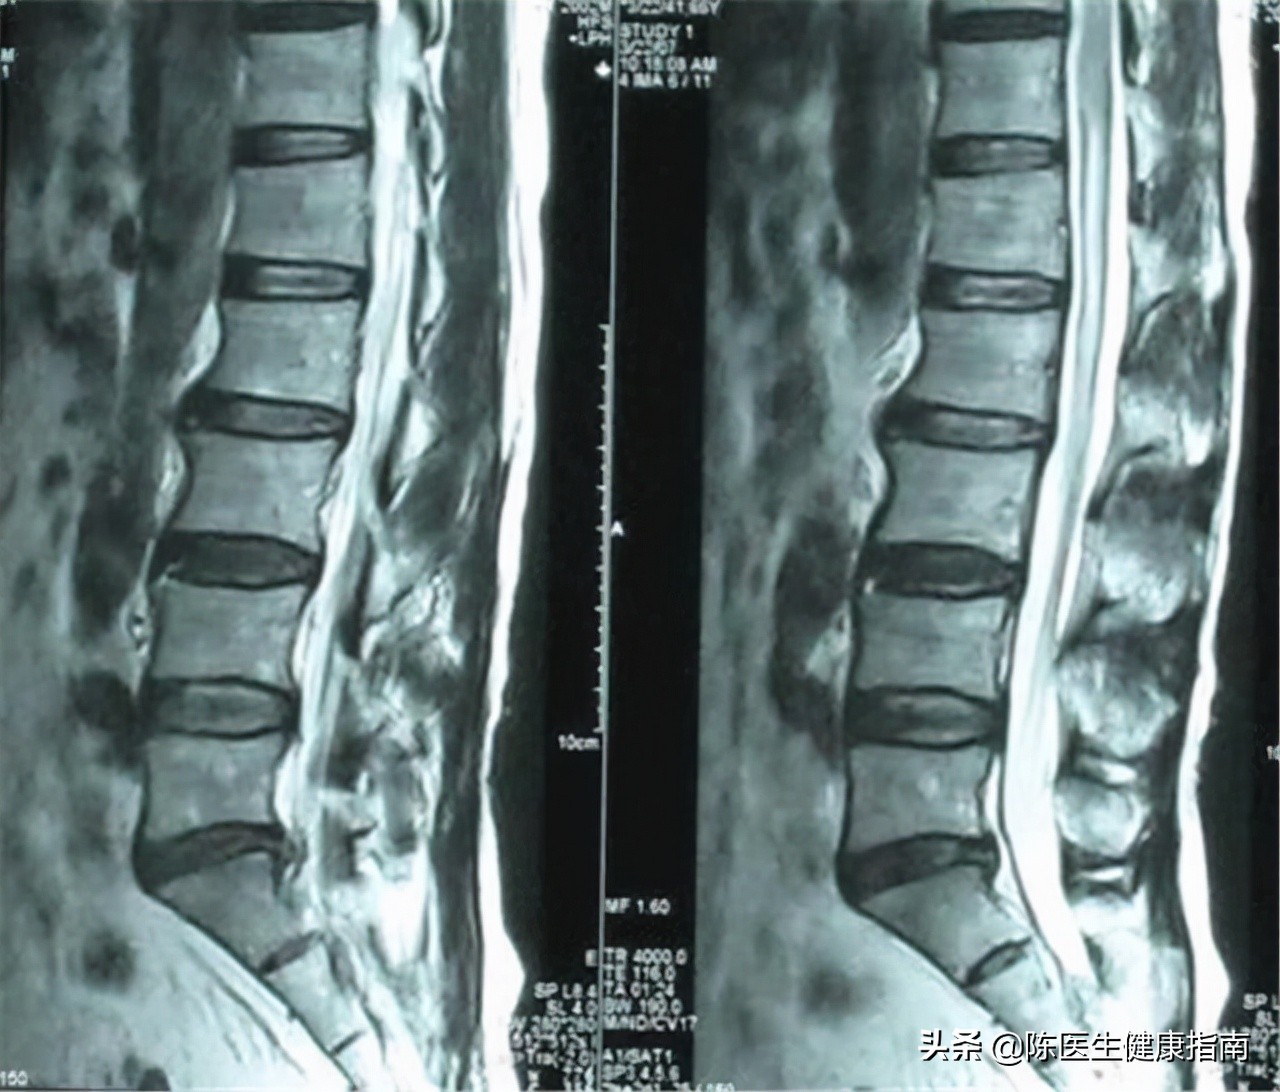

同时通过调节磁场,人体的各个剖面可以自由选择:像脊髓、椎间盘这些其他检查可能无法完全接近或比较难以接近的部位,通过核磁共振可以达到。

例如神经根、脊髓及神经节等部位通过矢状面、冠状面及横断面成像技术就可以很好的完成。而CT技术获得的均为垂直于人体长轴的横断面。

核磁共振对软组织,例如膀胱、直肠、子宫、阴道、骨、关节、肌肉等部位的检查优于CT,腰、颈椎间盘突出症等类似疾病,可通过 磁共振更好的观察到软组织的状况 , 但是对于对肺、肝脏、胰腺、肾上腺、前列腺的它的检测效果并没有优于X线或cT检查,对胃肠道的病变的检查不如内窥镜检查更加准确清晰。